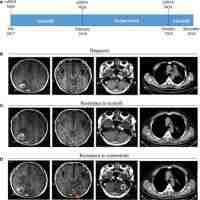

| Abstract | BackgroundLung cancer patients with sensitizing epidermal growth factor receptor (EGFR) mutations treated with osimertinib will eventually develop progressive disease (PD). The survival following PD varies greatly between patients, and no effective treatment strategy has been established. Furthermore, at the moment, no easily accessible and precise biomarker exists that can predict the survival after PD.MethodsWe analyzed blood samples drawn from non-small cell lung cancer patients harboring EGFR mutations that were treated with osimertinib. The levels of 92 circulating proteins were analyzed from plasma samples using a proximity extension assay (PEA). The results were evaluated with Gene Ontology (GO) enrichment analysis to reveal patterns of protein expression at progression while on osimertinib treatment.ResultsWe found that the expression of 7 proteins were significantly altered at PD, compared to a sample taken at osimertinib response. GO enrichment analysis demonstrated that most of the significant proteins were related to the immune system, specifically the adaptive immune response. Defining two groups of patients, based on the levels of circulating immune response proteins at PD, revealed significant differences in the overall survival (OS) after PD [hazard ratio (HR) =3.04; 95% confidence interval (CI): 1.24–7.45; P=0.0046].ConclusionsIn this study, we discover novel circulating biomarkers that can predict the OS after PD on osimertinib. These findings support the recent acknowledgement of the immune system’s importance in osimertinib resistance. |